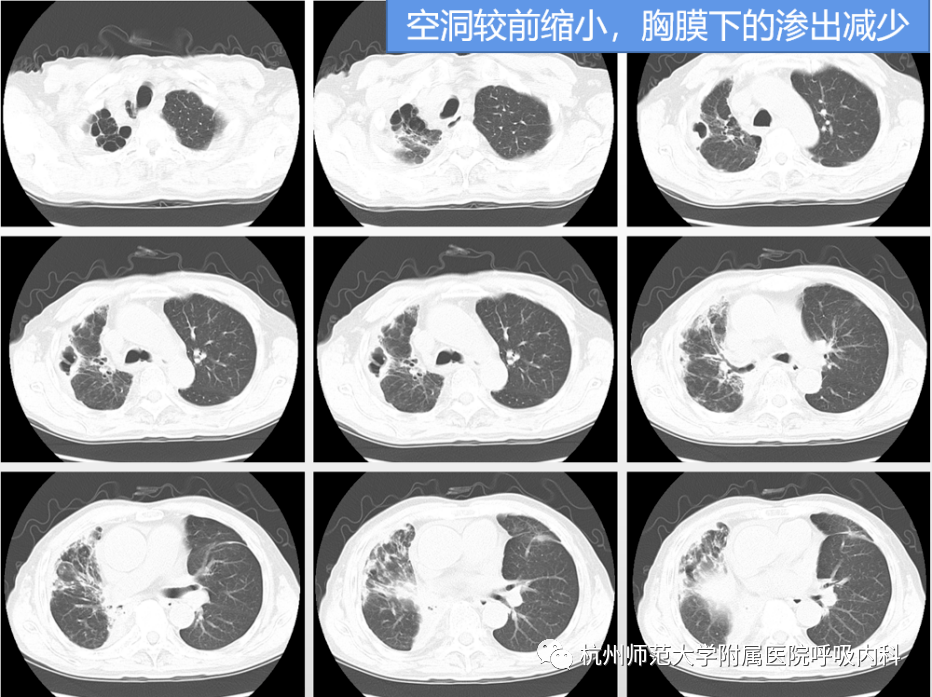

肺空洞ct图片,空洞型肺结核ct图片

空洞型肺结核ct图片

肺结核空洞ct图片

肺空洞愈合的ct图片

肺结核空洞ct图片解释